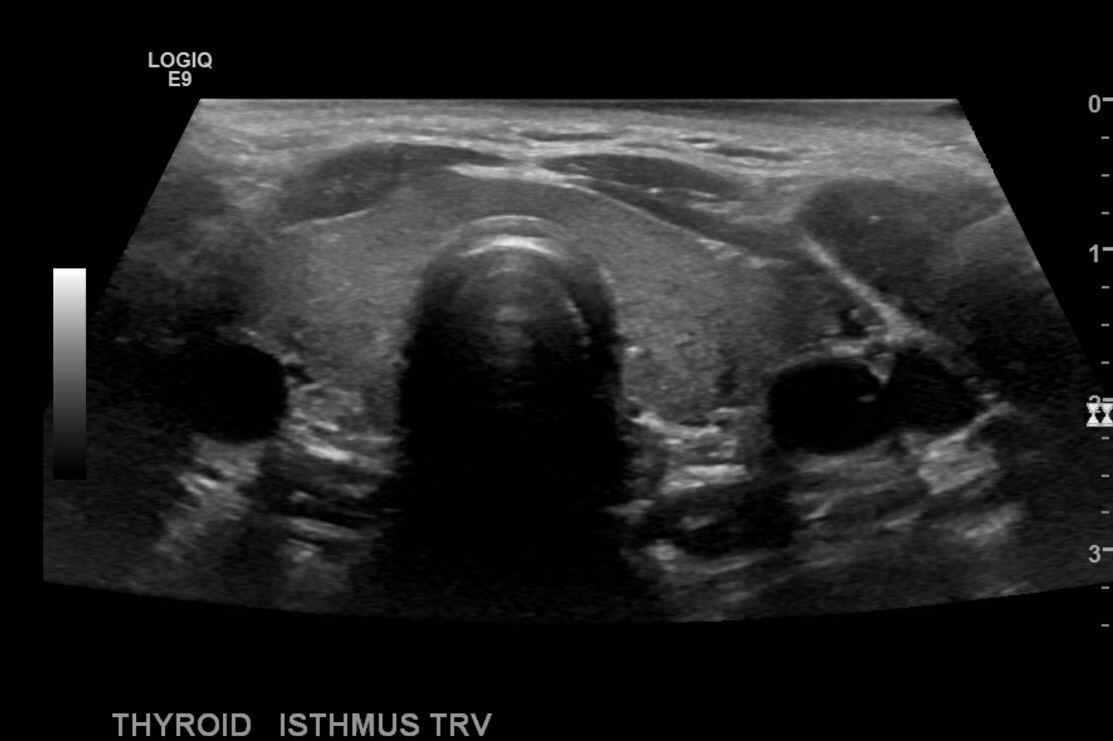

Begin in the midline neck transverse below the thyroid cartilage.

Take image of the thyroid at midline, sweep superior and inferior and measure the isthmus in anteroposterior dimension. Also place color doppler over the gland.